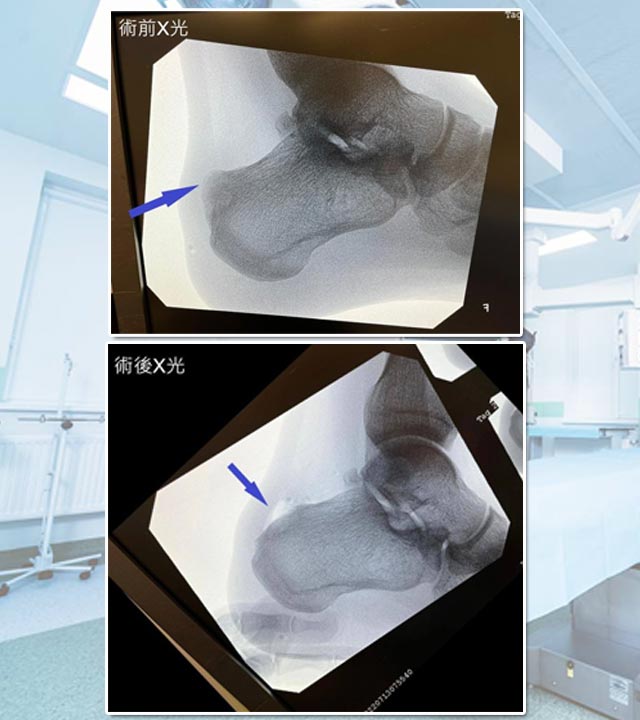

病人最終在X光檢查下,發現後腳跟位置先天骨頭增生突出,症狀學名為。由於先天骨頭形狀;再加上後天因素,長時間跳躍、行路、站立等動作,漸漸後腳跟骨增生與阿基里斯跟腱形成重覆磨擦,因而誘發腫脹發炎。

以手術方法將骨增生移除及磨平,只要將摩擦阿基里斯跟腱的骨刺移除,就能大大改善症狀。

除了將骨增生移除,阿基里斯跟腱的缺口也需要作修復及強化,術後需要以特製鞋子保護跟腱約4-6星期。